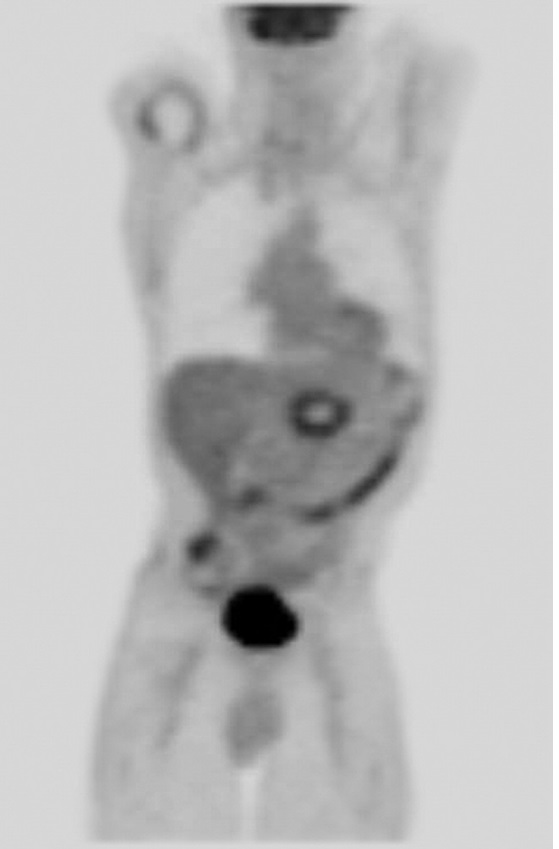

在随后两周的随访中,病人出现轻微间歇性疼痛,没有出现疲劳,发烧或其他症状。每次消融后24小时之内都使用对比增强磁共振成像(图3),第二次消融后的30天预期消融区没有出现增强。消融区的脉管系统尤其是脾动脉和肠系统上动脉保持明显不变的术前外表。血清肿瘤抗原在消融手术后30天从1500U/mL减少到404U/mL90天达到407U/mL。诊断后使用PET/CT成像(图4)如图所示出现了一个轻微的氟脱氧葡萄糖周边圈。虽然没有观测到参与肿瘤或节似疾病,但是在治疗后的三个月PET/CT扫描出了1.5cm的肝转移。因病变远离大血管在经皮RF消融后肝转移被成功治愈,然后开始吉西他滨化疗。RF消融两个月,诊断后六个月,磁共振成像显示腹部没有疾病恶化或复发。癌症病源19-9水平六个月减少到236U/mL。

PET/CT image at 3 months. Smooth marginal uptake is seen, which is an expected finding after ablation. There is no focal residual disease in the pancreatic bed. Focal left hepatic

uptake is not well seen on coronal projection.